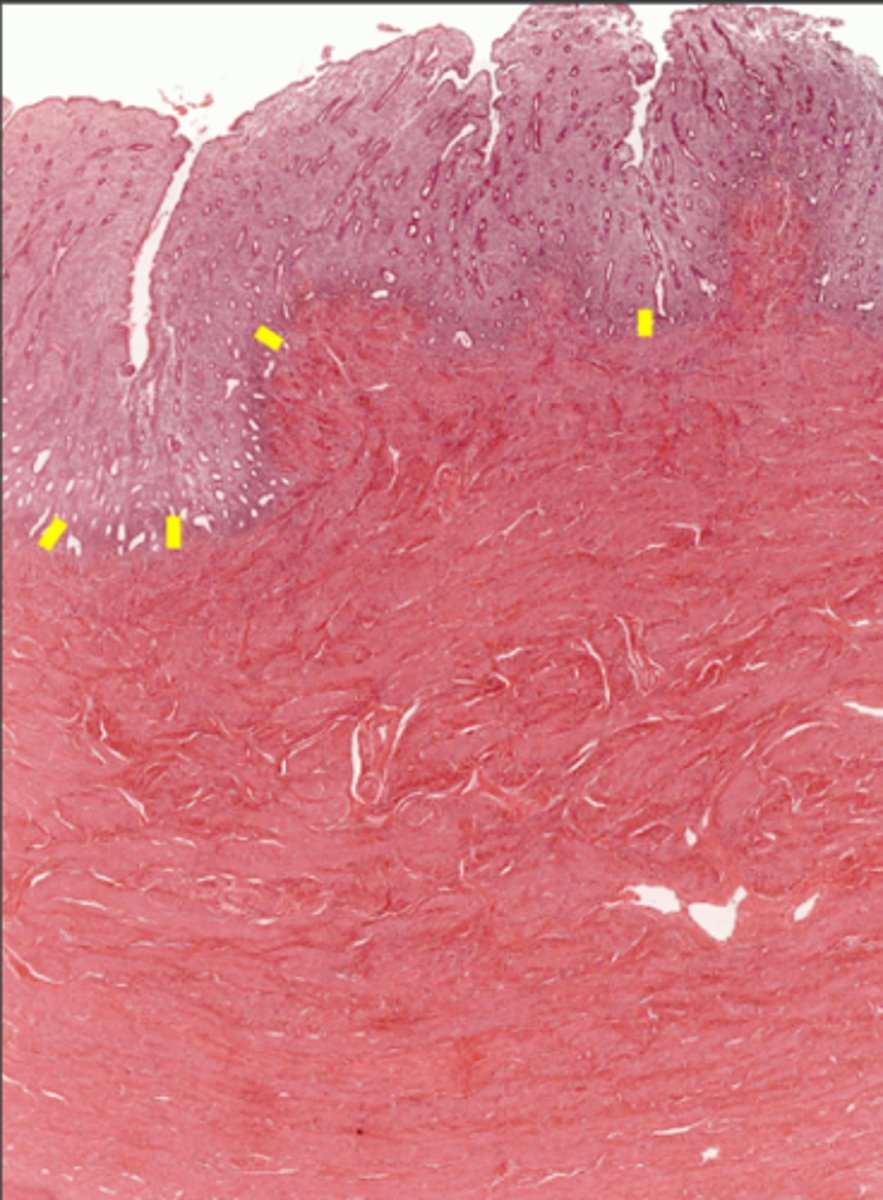

Perimetrium

Perimetrium

Myometrium

Myometrium

Endometrium

Endometrium